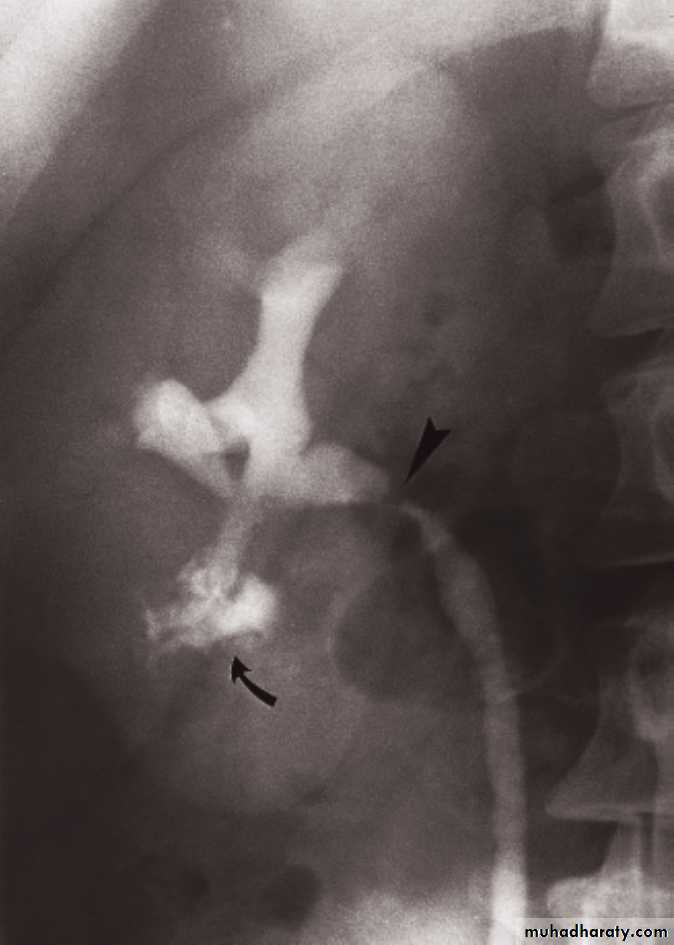

Urothelial tumors

Almost all tumors that arise in the PCS are TCC.Sometimes occur at multiple sites (so both PCSs and ureters should be examined).

IVU plays important role in their Dx.

Ddx of TCC on IVU are stones and blood clots.